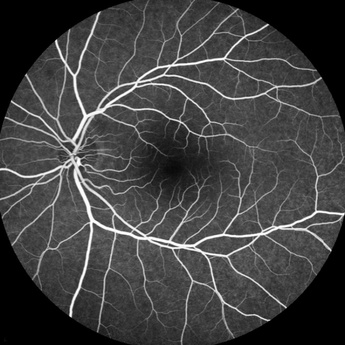

Kontrastfotografering af nethinden

Formålet med undersøgelsen er at afdække, om der er forandringer i dit øjes nethinde og blodkar. Undersøgelsen kaldes også fluorescein/ICG angiografi.

Ved undersøgelsen indsprøjter vi et kontraststof i en vene i din hånd, mens vi fotograferer din nethinde. Vi kan dermed iagttage og vurdere nethindens blodforsyning. Er du gravid eller har allergi, skal du på forhånd oplyse os om dette.